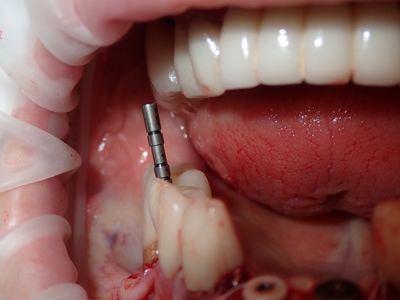

NSankhyan - immediate 13, impls 1121 and 25 with grafting

13 exo, loss of labial plate, implant placed buccal region grafted with sticky bone and collagen membrane soaked in prf fluid. 11/21 limited Labial-palatal width of bone, ridge split to 5mm, osteotomies prepared to about 2mm, remainder with densah drills, implants placed with ample bone, buccal grafted with same sticky bone. densah drills used for apical portion of 25 implant, soft bone, implant placed